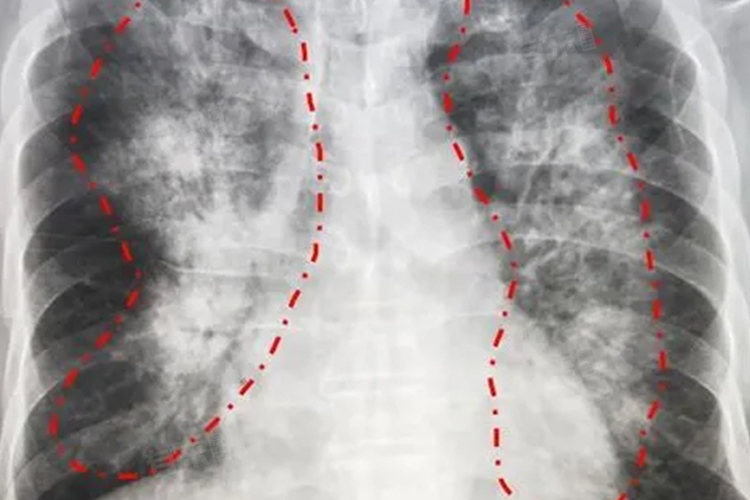

急性肺水肿是一种严重的临床综合征,其主要症状包括咳嗽咳痰、呼吸困难、紫绀、烦躁不安、心率血压改变等。

急性肺水肿通常由心功能不全、肺部疾病或其他原因引起,表现为肺泡和肺间质内液体积聚,导致气体交换障碍。该病起病急骤,病情凶险,需立即就医。治疗包括氧疗、利尿、扩血管等措施,以减轻肺部液体积聚,改善气体交换。